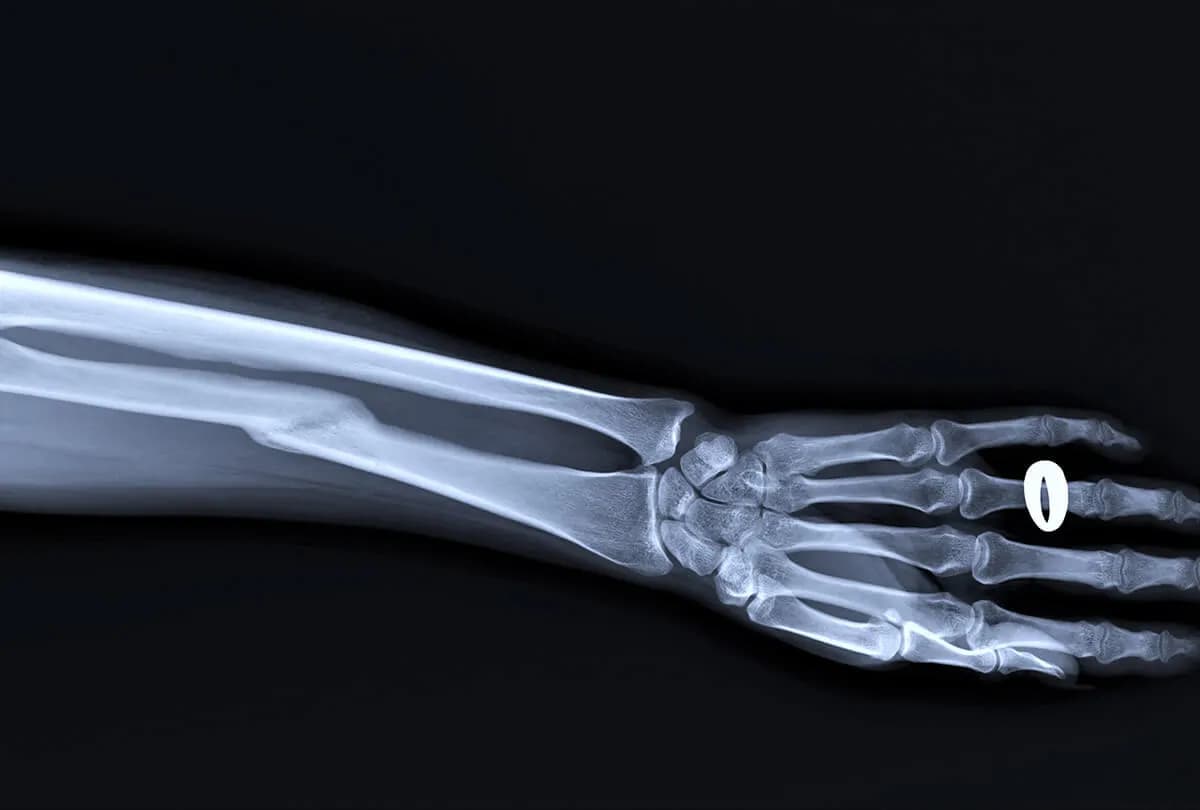

Złamanie kości promieniowej z przemieszczeniem: skuteczne leczenie

Dowiedz się, jak skutecznie leczyć złamanie kości promieniowej z przemieszczeniem. Poznaj objawy, rodzaje złamań i metody rehabilitacji. Sprawdź, kiedy konieczna jest operacja.